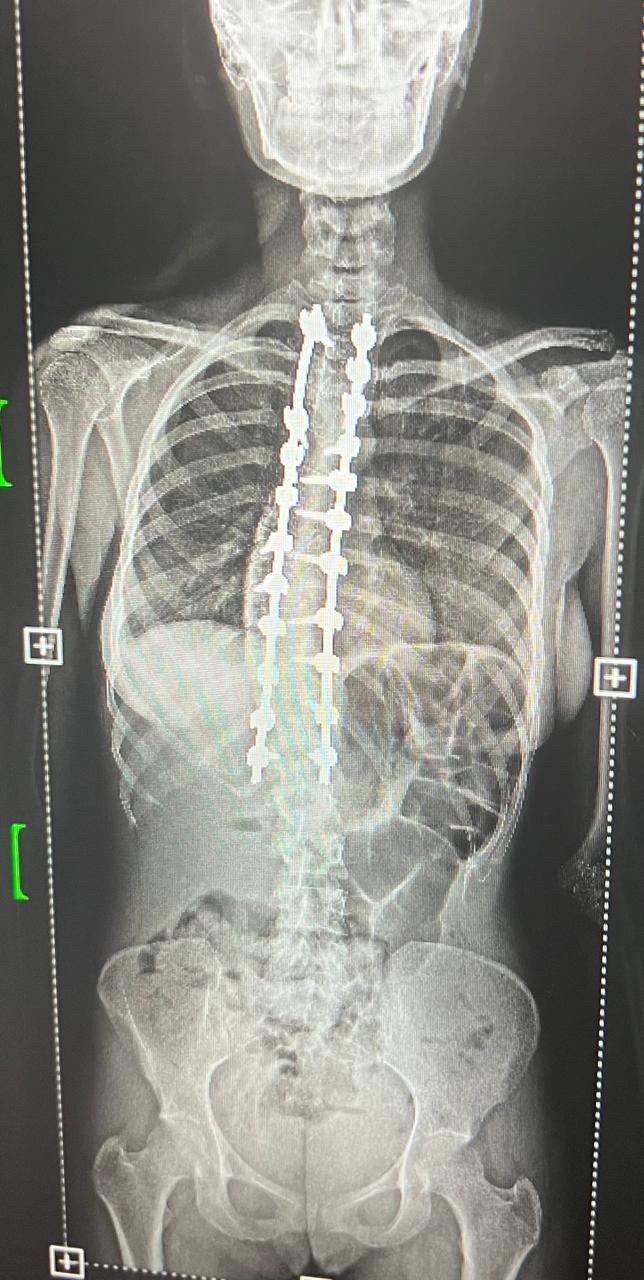

سجل مستشفى القطيف المركزي إنجازاً طبياً نوعياً بنجاح أول حالتين لتصحيح انحناء العمود الفقري، مستخدماً تقنيات المراقبة العصبية المتقدمة في جراحات استغرقت 8 ساعات.

وحقق قسم جراحة المخ والأعصاب والعمود الفقري بالمستشفى تقدماً لافتاً في التدخلات الجراحية الدقيقة، بعد تمكنه من إنهاء معاناة مريضين عبر إجراء عمليات تصحيح لانحناءات متقدمة في العمود الفقري لأول مرة.

وخضعت الحالتان لتقييم طبي شامل ودقيق تضمن إجراء كافة الفحوصات الإكلينيكية والأشعة المتخصصة، التي كشفت عن وجود تشوهات ودرجات انحناء متقدمة استوجبت التدخل الجراحي العاجل لتفادي المضاعفات.

واستعان الفريق الطبي بأحدث التقنيات العالمية في هذا المجال، معتمداً بشكل أساسي على أجهزة المراقبة العصبية الدقيقة لضمان أعلى معايير الأمان وسلامة الأعصاب الحساسة أثناء إجراء التعديل.

واستغرقت كل عملية نحو ثماني ساعات متواصلة من العمل الدقيق، نظراً لتعقيد الحالات وحاجتها لتنسيق عالٍ ولحظي بين جراحي العمود الفقري وفريق التخدير لضمان استقرار المريض.